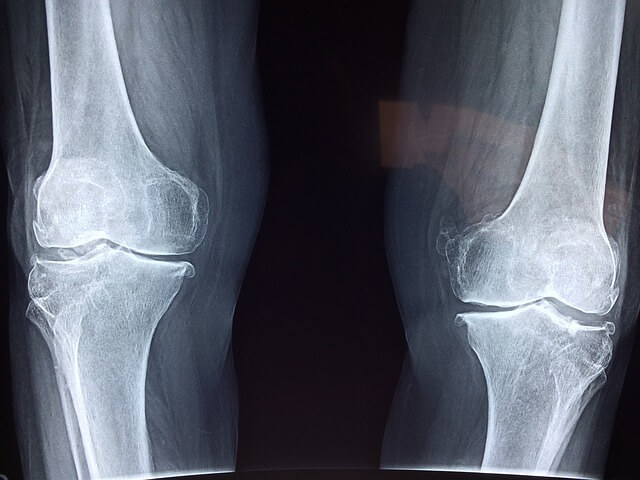

퇴행성 손가락 관절염은 손가락 끝마디에 주로 발생하며, 연골이 닳아 염증이 생기는 질환입니다.

관절염은 관절의 염증을 일으켜 통증과 부기를 초래하며, 손가락 끝마디가 굵어지고 돌출되는 특징이 있습니다.

류마티스 관절염은 자가면역 질환으로, 손가락 중간 마디와 손가락 시작 부분에 염증이 생깁니다.

손가락이 뻣뻣하고 아프며, 부기와 홍반이 동반될 수 있습니다. 주먹을 꽉 쥘 수 없는 경우도 많습니다. 치료에는 스테로이드, 항류마티스약, 생물학적 제제가 사용됩니다.